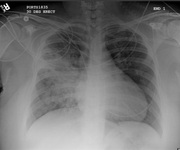

Neumonía adquirida en la comunidad en adultos (no COVID-19)

derrame pleural del lado izquierdo

De la colección del Dr. R Light. Usado con autorización